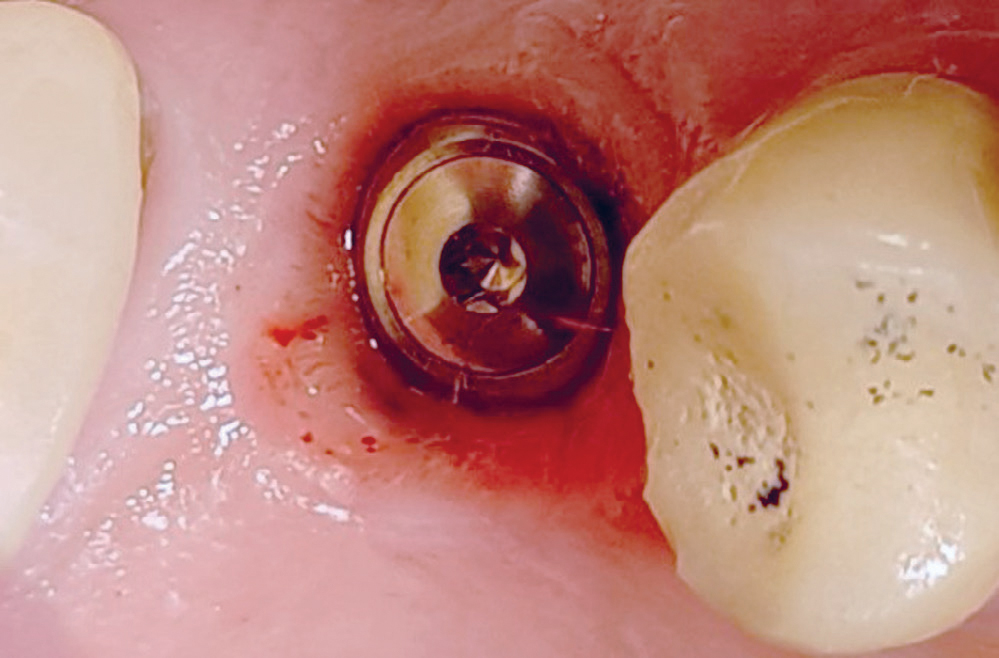

Behandling: i januar 2014 ble det innsatt et implantat, (ITI standard plus, «wide neck») med lengde 8.0 mm. Tilhelingen forløp uten komplikasjoner og røntgenbilde tatt 3 måneder senere indikerte osseointegrasjon av implantatet (figur 4). Det ble deretter tatt avtrykk og fremstilt en krone. Retensjonsskruen ble trukket til med 35Ncm. I tidsrommet april 2014 til april 2018 ble det ikke utført tannbehandling som endret okklusjonsforholdene i tannsettet. Etter 4 år i funksjon merket pasienten lette symptomer i implantatområdet og henvisende tannlege diagnostiserte svak mobilitet. Ved undersøkelse hos spesialist i periodonti april 2018 var det ikke mulig å måle lommer rundt implantatet og heller ikke påvise blødning ved sondering. Klinisk mobilitet grad I ble påvist i bucco-palatinal retning. Okklusal slitasje ble verifisert ved hjelp av blåpapir og overbelastning ble antydet som mulig årsak til implantatmobilitet. Pasienten ble forelagt to behandlingsalternativer: fjerne implantatet og eventuelt vurdere nytt implantat etter 12 ukers tilheling, eller forsøke å bevare implantatet etter først å ha fjernet kronerestaurering og så observere om implantatet re-osseointegrerte. Pasienten valgte det siste alternativet. Kronen ble fjernet og submucosal tilhelingstopp montert (figur 5).

Figur 5. Implantatkronen 16 er fjernet og submucosal tilhelingstopp montert. Rolige mucosale forhold rundt implantatets coronale del.